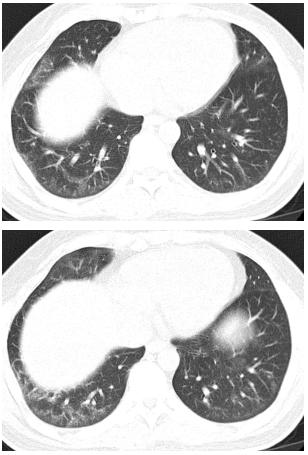

说完,委托人递过了肺CT的结果:双肺纹理增粗,透光度不均,双下肺见斑片状密度增高影,边缘模糊,双下肺可见细网格状影。

图1:肺CT结果

后来,委托人接受了糖皮质激素、免疫抑制剂麦考酚酯、羟氯喹以及对症支持治疗,症状逐渐改善,心肌酶变为正常,胸部CT斑片影较前吸收,双下肺仍可见细网格状影。

图3:治疗一段时间后肺CT结果